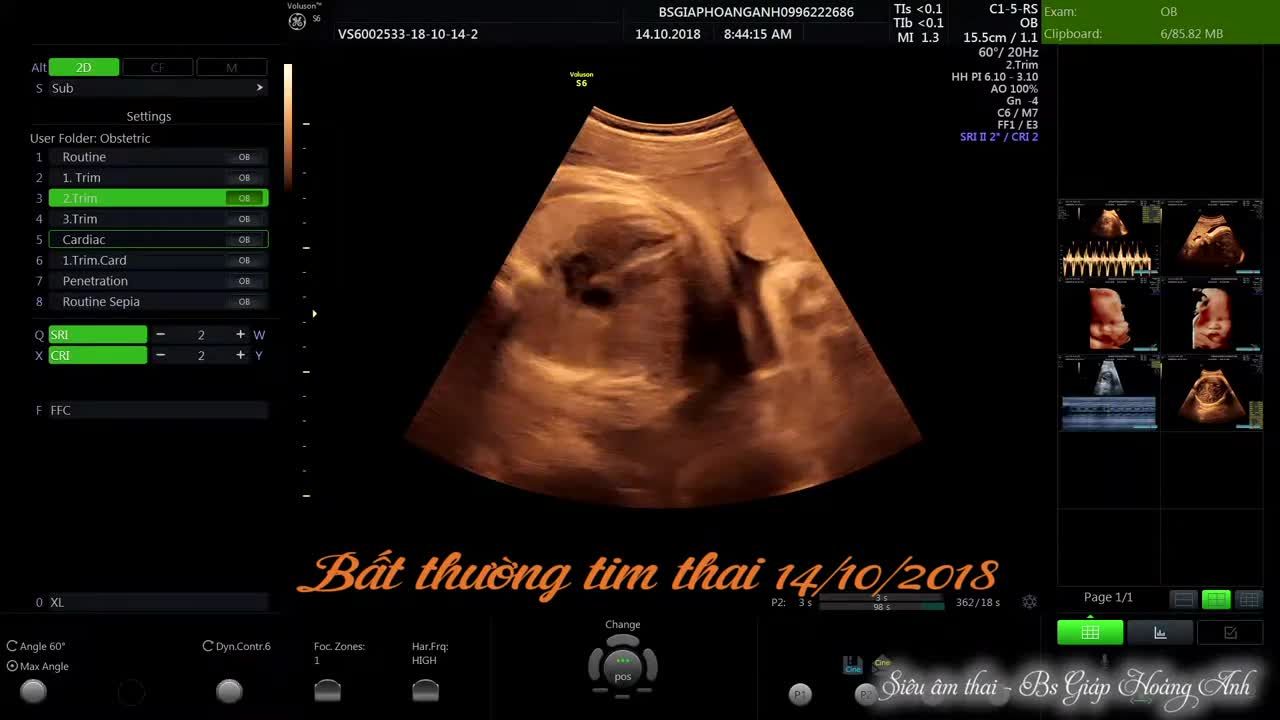

Bác sĩ ơi, hôm qua em đi siêu âm thì bảo bé em bị màng ngoài tim có dịch. Nhờ bác xem giúp em với. Nếu mà bé cứu được thì sau này có để lại di chứng gì không ạ? Do em bé đầu nên không biết sao